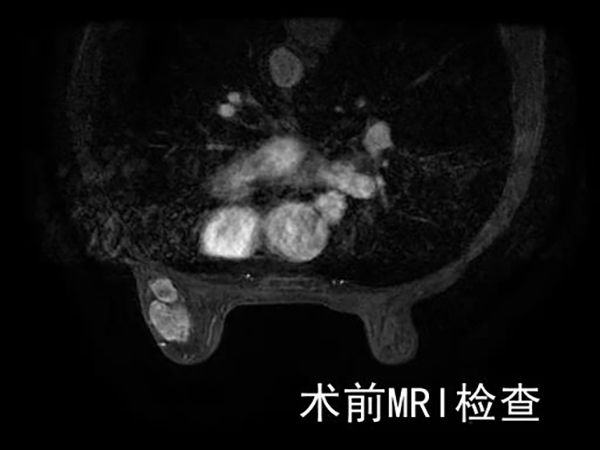

今年已86岁高龄的刘女士,近日因“左乳肿块一年,逐渐增大”前来医院普外科门诊治疗。普外科医生佟凡在接诊后,发现患者不仅体重过轻、高龄,还长期吸烟,乳腺肿块的性质也需进一步明确诊断。在入院后,患者接受了包括肺功能在内的多项常规检查。鉴于患者长期吸烟,肺功能检测结果表明她患有重度阻塞性通气障碍。与此同时,左乳肿瘤被诊断为乳腺癌。好消息是在进行了一系列全面的全身检查后,并未发现明显的转移迹象。为了防止病情恶化,对于这位高龄患者而言,手术治疗似乎是最合适的治疗方案。

▲患者术前查体及影像学检查